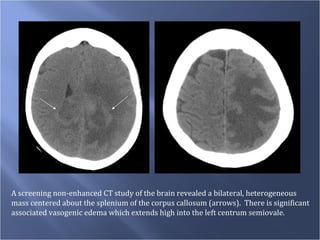

A screening non-enhanced CT study of the brain revealed a bilateral, heterogeneous  mass centered about the splenium of the corpus callosum (arrows).  There is significant  associated vasogenic edema which extends high into the left centrum semiovale.

A screening non-enhancedCT study of the brain revealed a bilateral, heterogeneous mass centered about the splenium of the corpus callosum (arrows). There is significant associated vasogenic edema which extends high into the left centrum semiovale.